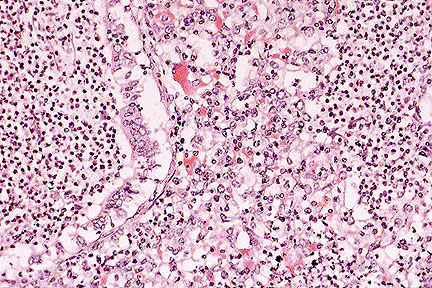

Granulomatous dermatitis; multinucleate giant cells often contain mite fragments. (HE, 400X, 156K)

One section of skin was examined. Mild superficial hyperkeratosis was noted. Mild focal epidermal hyperplasia was also evident. Moderate perivascular accumulations of eosinophils intermixed with lymphocytes and occasional plasma cells were noted within the dermis. Mild to moderate apocrine gland dilation and dermal edema were also noted. One large focal elevated dermal mass was evident, composed of a central cystic site containing amorphous eosinophilic material intermixed with cellular debris and rimmed by large accumulations of lymphocytes intermixed with macrophages, plasma cells, eosinophils, epithelioid cells, multinucleated giant cells and immature fibrous connective tissue. Numerous elongated organisms were evident within the cystic center of the mass and within the adjacent inflammatory cellular infiltrate. The organisms were approximately 100 to 300 æm in length and contained numerous small basophilic spherical bodies internally. Many of the organisms had 4 pair of legs that appeared in the section as short eosinophilic appendages on the ventrolateral surface of the anterior aspect of the body. The mass appeared completely excised.

Demodectic mites are normal inhabitants of hair follicles or sebaceous glands of domestic animals and humans. Demodectic mange in cattle occurs worldwide and is produced by 3 Demodex species: D. bovis, D. ghanensis and one unnamed parasite. Gross lesions are characterized by multiple cutaneous nodules containing thick waxy material. The masses may rupture, producing an abscess or a granuloma within the skin. Histologically, the nodules represent follicular cysts that contain numerous demodex mites and keratin. Perforation or rupture of the follicular cyst can produce a severe focal granulomatous inflammatory reaction containing degenerating and mineralized segments of parasites rimmed by numerous lymphocytes, plasma cells, eosinophils, epithelioid cells and multinucleated giant cells.

AFIP Diagnosis: Haired skin: Granuloma, with eosinophils and central demodectic acarids, Holstein, bovine.

Conference Note: In cattle, demodecosis presents grossly as multiple cutaneous nodules over the shoulders, neck, dewlap, and muzzle. The number of nodules may vary from a few to several hundred. Histologically, the nodules are follicular cysts, lined by squamous epithelium, and filled with keratinous material and large numbers of mites. Rupture of the cyst induces a granulomatous reaction as seen in this case. Demodectic mange in cattle renders the hide unsuitable for leather production and is mainly of economic importance; however, in Africa and Madagascar, demodectic mange may be generalized and fatal.